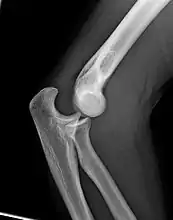

Left: Lateral X ray of a dislocated right elbow

Right: AP X ray of a dislocated right elbow